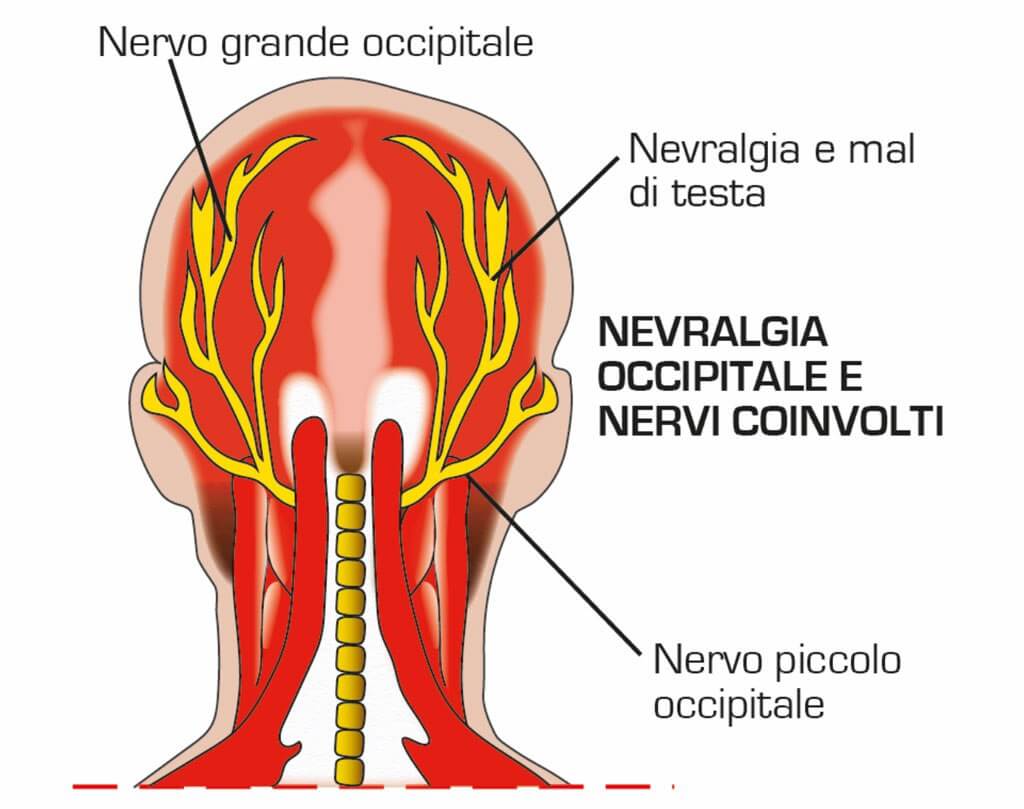

Argomenti Come si curano le nevralgie della testa e del Collo di tendenza

Viral Mal di testa da cervicale o dietro agli occhi, collo, muscoli diventato virale